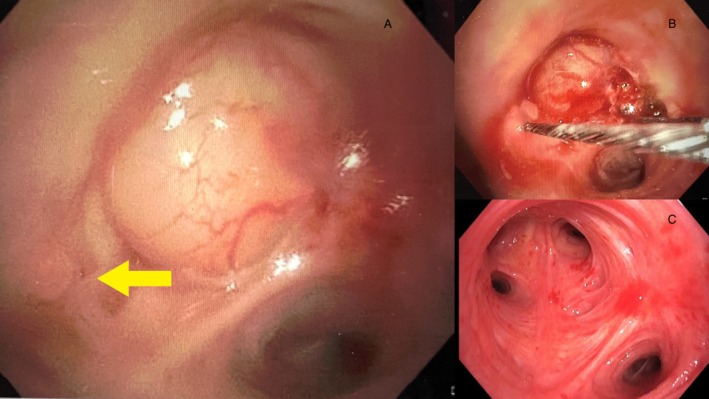

Pulmonary leiomyomas are rare benign tumours of bronchial smooth muscle origin. They can present either in the lung parenchyma or tracheobronchial tree, with 45% being located endobronchially. Endobronchial leiomyomas typically present with airways symptoms such as dyspnoea, cough, and obstructive pneumonia. Traditionally, endobronchial leiomyomas were managed surgically with lobectomy or pneumonectomy but, increasingly, management has shifted to bronchoscopic resection with different endoscopic techniques described in the case report literature. Most reports include outcomes ranging from 3 to 6 months following bronchoscopic resection. We present a case of a 40-year-old female with a left upper lobe (LUL) leiomyoma who presented with complete LUL collapse consolidation. Bronchoscopic resection was performed using a combination of diathermy snare, cryo-recanalisation, and argon plasma coagulation (APC) which resulted in excellent restoration of the LUL patency. Annual bronchoscopy surveillance over 7 years confirmed durability of the procedure with no recurrence detected.